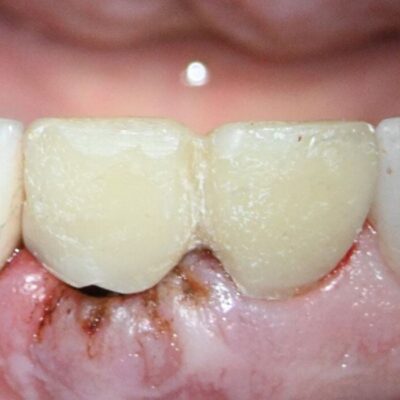

As the implant was placed by Dr. K. about 8 years ago, he was referred there for recovery of the fractured zirconia abutment and abutment screw. Recovery of fractured zirconia abutments from Ankylos implants are almost always difficult and tricky due to the tight conical connection at 5.7 degrees and the hardness of the zirconia. Because the abutment screw is free floating (the through bore is smaller than the threads), this presents an additional roadblock to recovery. Evidently, the patient was seen for about 1.5 hours, and while not excessive in my experience, there was only partial recovery of the fractured components. On examination, it was clear while some of the conical portion of the zirconia abutment had been removed, so had some of the implant top. The decision was made to proceed with finishing the recovery as I felt the remaining portion of the conical connection was enough to provide a stable abutment to implant connection. As the area had been flapped the previous day the proximal sutures were left intact and only a small amount of tissue contouring was needed to provide adequate access to visualize the implant top. The site was photographed prior to proceeding with further recovery efforts. As the screw head had already been removed along with the top two thirds of the conical abutment, the bottom portion of the conical abutment was concentrically removed with a surgical length high speed round diamond under microscope visualization. This was done to the level of the indexing splines which start approximately 3mm below the top of the implant. At that time, the zirconia splines became visible, and several small chunks of zirconia were retrieved. With careful manipulation of the screw fragment with an endodontic explorer and modified endodontic spoon, the screw was mobilized and maneuvered so a surgical length ¼ round bur could be placed on the screw outside diameter (OD), in an open implant spline. Again, with microscope guidance, the screw fragment was recovered along with the remaining zirconia fragments. The implant was cleaned, and the supplied healing abutment was placed finger tight. The recovery was completed without further damage to the implant. The patient’s existing provisional was modified to fit the healing abutment contours and was recemented with Tempbond clear, as it appeared to be the cement that was previously used. The patient was dismissed to return to Dr. S. for continuation of his restorative treatment plan.

Due to the initial recovery effort, without a doubt, the implant top was altered and some of the conical connection was lost. I would think a custom titanium abutment would be preferable to zirconia. This abutment connection is small to begin with, 3.97sq mm at the implant top, and a strong argument can be made to avoid zirconia altogether in most if not all Ankylos applications. With the loss of approximately .5-.6mm of conical connection height this connection will become even smaller, and more prone to fracture. As stated earlier, I believe the stability of the abutment to implant connection will be stable in regard to abutment and screw stability, but that is due to the 5.7-degree conical interface and its ability to protect the screw. Use of a stronger abutment material that is more resistant to torsional loads might compensate for the decrease in surface area size. Caution should be taken to avoid non-OEM abutment components as several have larger through bore designs to avoid the laser assembled free floating screw design which will decrease the abutment strength even further. C.A.M.